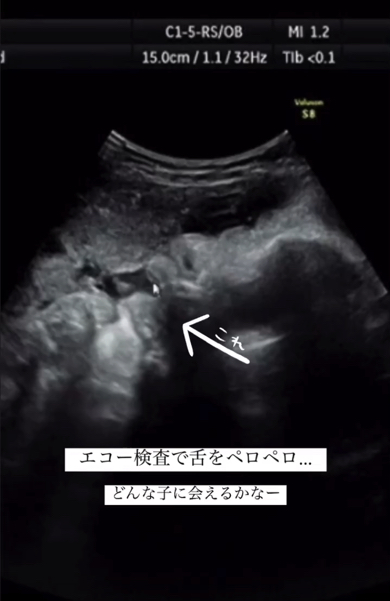

妊娠中のエコー検査で、両親に向かって「あっかんべー」をしていた赤ちゃん。無事に産まれ、2時間後の様子を見てみると……? かわいくてちょっと不思議な赤ちゃんの姿を捉えた動画がInstagramに投稿され、記事執筆時点で47万回再生されるなど多くの注目を集めています。

出産予定日を過ぎた、41週目の検診でのこと。赤ちゃんがなかなか生まれてこないので、よっけさん夫妻は不安な気持ちで検診に臨んでいました。しかし、おなかの中をエコーで見てみると、赤ちゃんはパパとママが思わず笑ってしまう行動をしていたのです。それは小さな舌をペロペロと出し入れし、まるで「あっかんべー」をするような動きでした。

生まれてから2時間後に撮影した動画を見てみると……なんと、赤ちゃんは舌をペロペロと動かしています! それは、おなかの中にいるときにエコーで見せてくれた動作と全く同じものでした。練習した成果を披露しているみたい……!